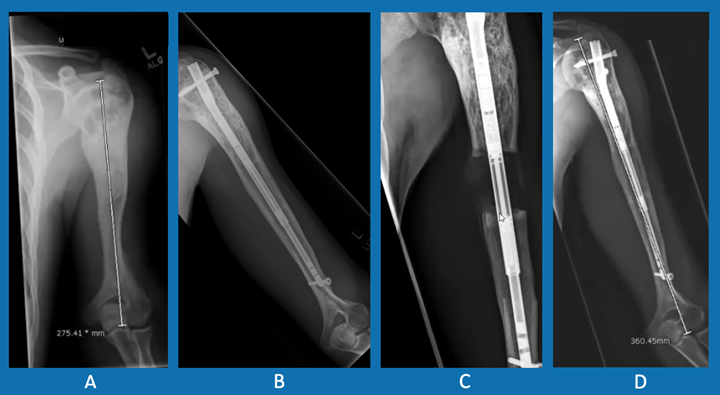

There are two types of limb-lengthening devices. One type is worn on the outside of the arm or leg. The other is an internal device that is more precise and reduces the risk of complications and infection.

External fixators are worn on the outside of the limb and are attached to the bone by pins. The patient or family adjusts the device daily to increase the distance between the two ends of bone. Once the correct length is reached, the device remains on the leg or arm while the new bone hardens and becomes strong. The device is then surgically removed.

The internal fixator (PRECICE Nail) is a nail that is surgically inserted inside the bone after the osteotomy. Using an external magnet that causes the nail to expand, the patient or family slowly lengthens the bone a tiny amount each day until the desired length is reached. Like the external fixator, the internal fixator is removed once the limb has been lengthened and new bone has formed.